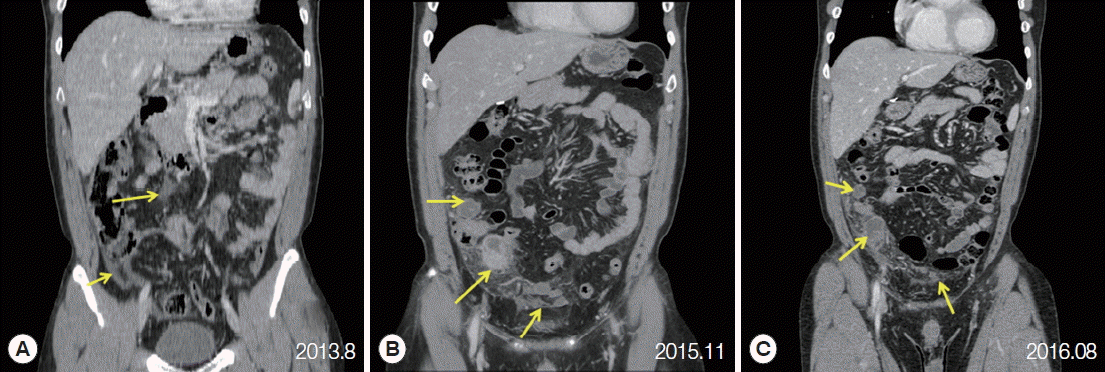

At 2 weeks before admission, the patient reported abdominal pain for the third time. The pain started over the whole abdomen, and later it was localized at the right lower quadrant area. The patient complained of continuous pain and rated its intensity as 6 to 7 on a scale of 0 to 10. This time he felt febrile sense and chills. Other gastrointestinal symptoms, such as anorexia, nausea, vomiting, and diarrhea were absent. On examination, localized tenderness and rebound tenderness was found at the right lower quadrant area. A complete blood count showed white-cell count 5,800×103 per mm3 with 56.7% of neutrophils and 3.3% of eosinophils. Total bilirubin was slightly increased as 1.5 mg/dl, and the results of other liver function tests, such as aspartate aminotransferase, alanine aminotransferase, alkaline phosphatase, and glutamyl transferase were within normal range. C-reactive protein was elevated to 4.66 mg/dl. The chest radiography showed no active lung lesions. The repeated CT of the abdomen and pelvis showed that the majority of the previous peritoneal lesions remained although the overall extent of intra-abdominal abscesses and peritoneal fat infiltration was slightly decreased. Colonic wall thickening or enhancement was not definite (Fig. 1).

Here, we presented a case of peritoneal paragonimiasis who suffered from recurrent abdominal pain. Since the thick-walled cavitary lesions were adjacent to the cecum on abdominal CT, recurrent diverticulitis and intra-abdominal abscess were initially considered. Only after the surgery, paragonimiasis was diagnosed based on the pathologic findings and subsequent serology.

When the abdominal pain is localized to the right lower quadrant, usual differential diagnosis includes acute appendicitis, diverticulitis, colitis, and inflammatory bowel diseases. Some of these diseases can cause recurrent episodes. For example, underlying colonic diverticulosis could result in repeated diverticulitis and unresolved vascular problem can cause recurrent ischemic colitis. In our case, the initially identified lesions on CT were peritoneal fluid dispersion with fat infiltration. They developed into thick-walled cavitary lesions containing dirty fluid or debris over 27 months and remained in the similar position. The chronic nature of the lesions and an absence of diverticulosis in colonoscopy suggested some kinds of chronic peritoneal inflammatory diseases, including parasite infections. The definitive diagnosis was made as peritoneal paragonimiasis after a surgery.